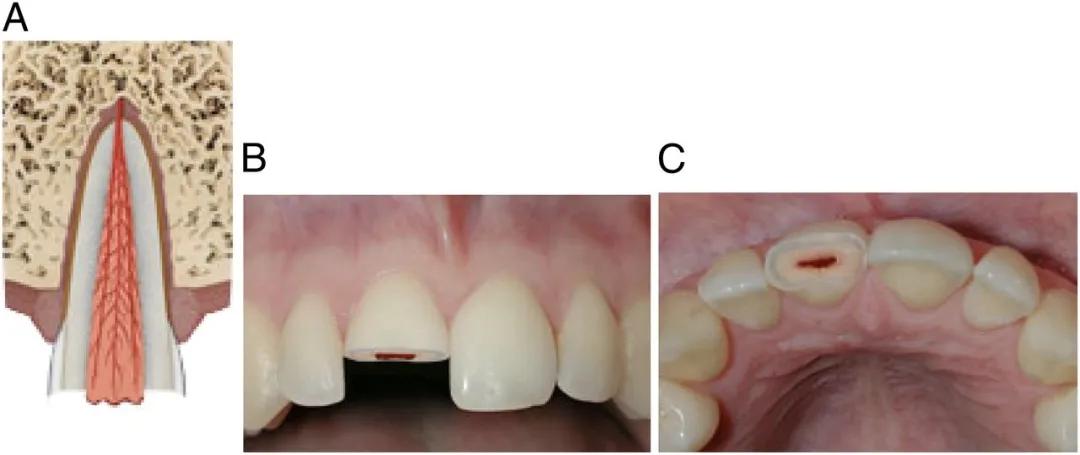

1、牙齿摔“歪”

摔歪的牙齿通常是牙齿尖往里(舌侧方向)歪。

侧脱位

严重的牙齿可能摔“短”一截,甚至摔没了,整颗牙直接“楔”进牙槽骨里。

入侵式脱位

摔歪的牙齿,一般伴有疼痛、松动、出血,同时出现咬合障碍,家长没有什么急救方法,能做的就是尽快就诊。

脱位幅度小的,医生可能会什么都不做,等牙齿自己复位;也可能手动把牙齿复位,然后等它自己长好;严重的,可能上夹板固定,跟处理骨折一样;再严重的,可能直接拔掉。